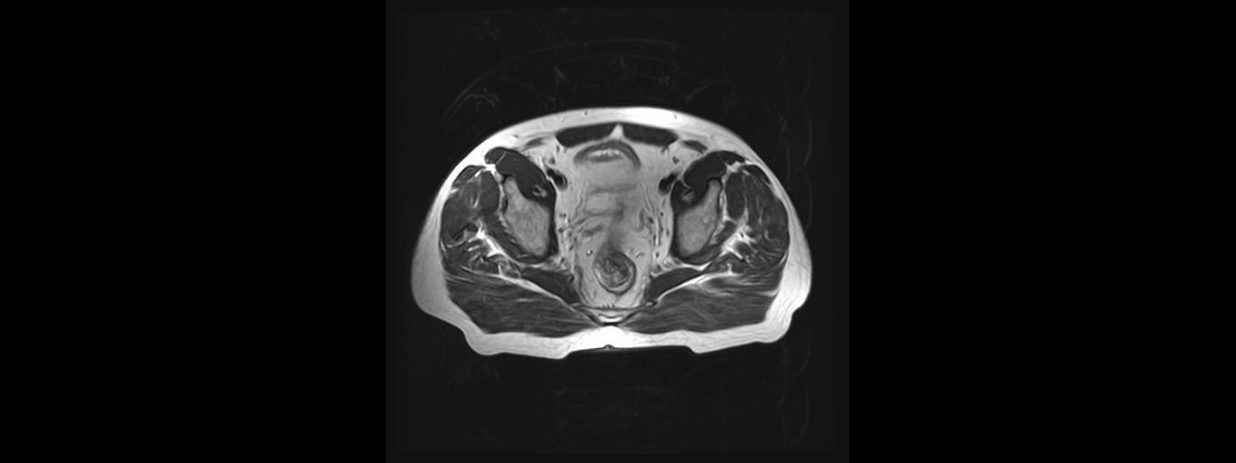

A continuación puedes consultar información general acerca de algunos de los estudios de Resonancia Magnética que tenemos disponibles, solamente da un clic en la imagen deseada: